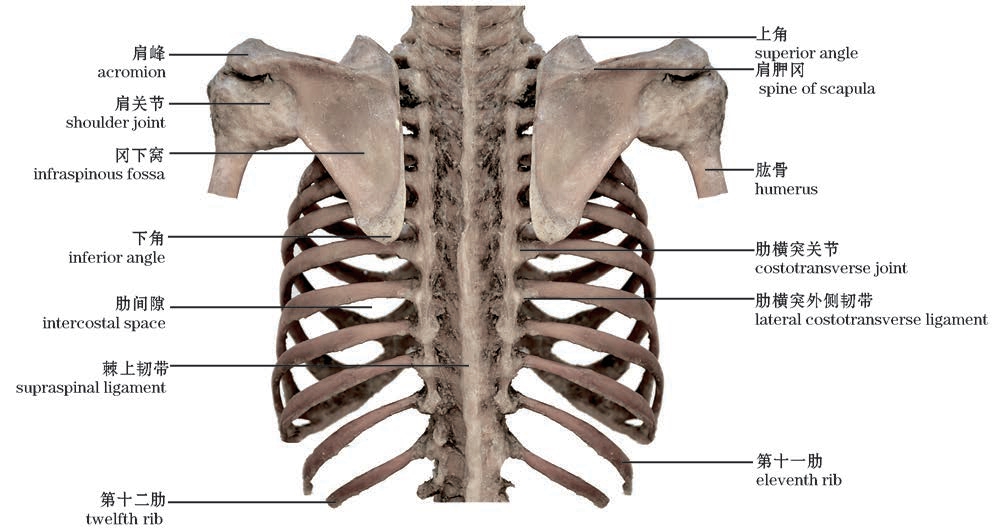

图2-16 胸廓与上肢带骨(后面观)

The thoracic cage and the bones of shoulder girdle(Posterior view)